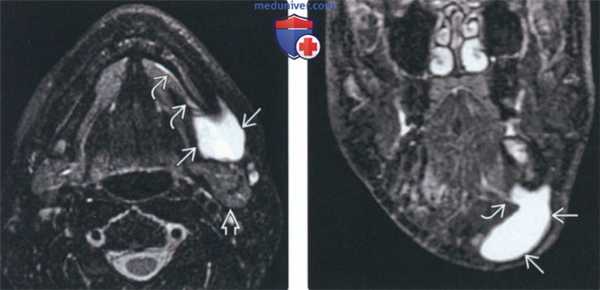

(Слева) МРТ Т2ВИ FS, подросток с рецидивирующей припухлостью в поднижнечелюстной области. В прошлом пациенту дважды выполнялась аспирация содержимого кисты. Определяется образование В с четкими контурами и гиперинтенсивным сигналом, которое находится кпереди от поднижнечелюстной железы и латеральнее челюстно-подъязычной мышцы. Признак «хвоста» лучше всего виден на Т2ВИ.

(Справа) МРТ Т2ВИ FS, коронарная проекция. Латеральная погружная ранула, которая представляет собой крупное кистозное образование поднижнечелюстного пространства. Часть ранулы (признак «хвоста») проходит через дефект в челюстно-подъязычной мышце.

3. МРТ при рануле:

• Т1ВИ:

о Гипоинтенсивный однородный сигнал (подобный ликвору)

• Т2ВИ:

о Гиперинтенсивный однородный сигнал (подобный ликвору)

• Т1ВИ с КУ:

о При отсутствии инфицирования контраст в стенках не накапливается или накапливается слабо

о Инфицирование в настоящий момент или в прошлом => утолщение стенок, возможно изменение сигнала на Т1 и Т2ВИ

о Т2 ВИ оптимальны для визуализации признака «хвоста»